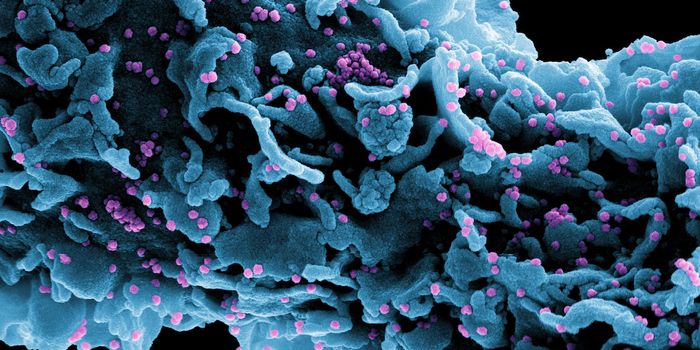

APR 04, 2022Cell & Molecular BiologyAbout 1.5 million new HIV infections are thought to have occurred last year, and while COVID-19 has dominated concerns a ...

FEB 21, 2022Cell & Molecular BiologyTwo people have been cured of HIV, and now, a US woman joins them. In this third case, stem cell transplants were being ...